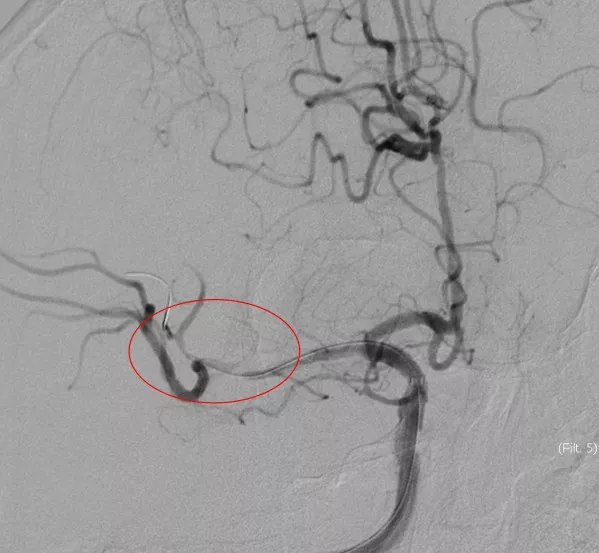

5MIN后

赛诺 2.0*15mm球囊扩张

5MIN后

赛诺 2.0*15mm球囊扩张